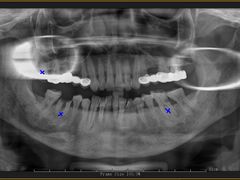

• 牙博士口腔品牌连锁(杨浦店)

• -牙博士口腔品牌连锁(杨浦店)